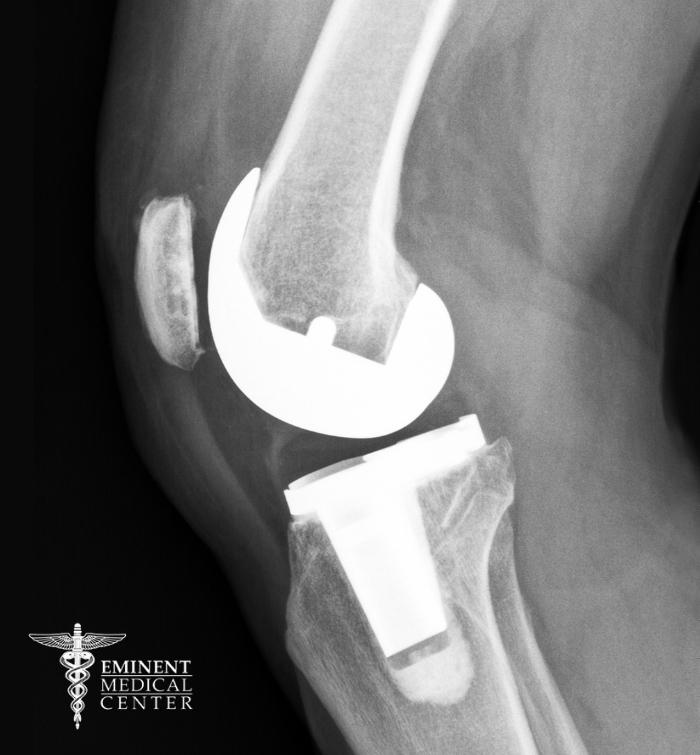

Knee replacement surgery, also known as knee arthroplasty, is a surgical procedure that replaces a damaged knee joint with an artificial joint composed of metal and plastic. The goal is to improve knee function, increase range of motion, and relieve pain caused by conditions like rheumatoid arthritis, chronic inflammation, or a serious knee injury.

During total knee replacement surgery, the surgeon removes worn-out articular cartilage, reshapes the bone, and inserts a knee prosthesis to create a smoother, more stable joint. In some cases, partial knee replacement may be recommended if only one part of the knee joint is affected. This orthopedic surgery in Richardson and Dallas, TX, is one of the most common and successful types of joint replacement performed today.

During your knee replacement surgery at Eminent Medical Center, your orthopedic surgeon will begin by making an incision over the knee joint to access the damaged areas. Worn articular cartilage, bone surfaces, and any damaged tissue are carefully removed and replaced with a custom-fitted knee prosthesis made of metal and plastic.

Depending on the extent of the damage, your surgeon will perform either a partial knee replacement or a total knee replacement. The goal is to restore smooth knee motion, improve knee function, and provide lasting pain relief.